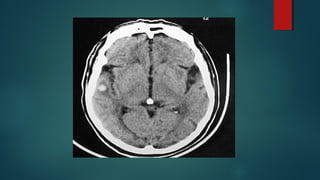

Este documento es el programa para un taller de imágenes del curso de emergencia 2015 impartido por el Dr. Víctor Delgado. El taller se centra en el uso de imágenes médicas para el diagnóstico y tratamiento de pacientes en coma traumático según la base de datos de Marshall. El Dr. Delgado es el único instructor repetido a lo largo del documento.